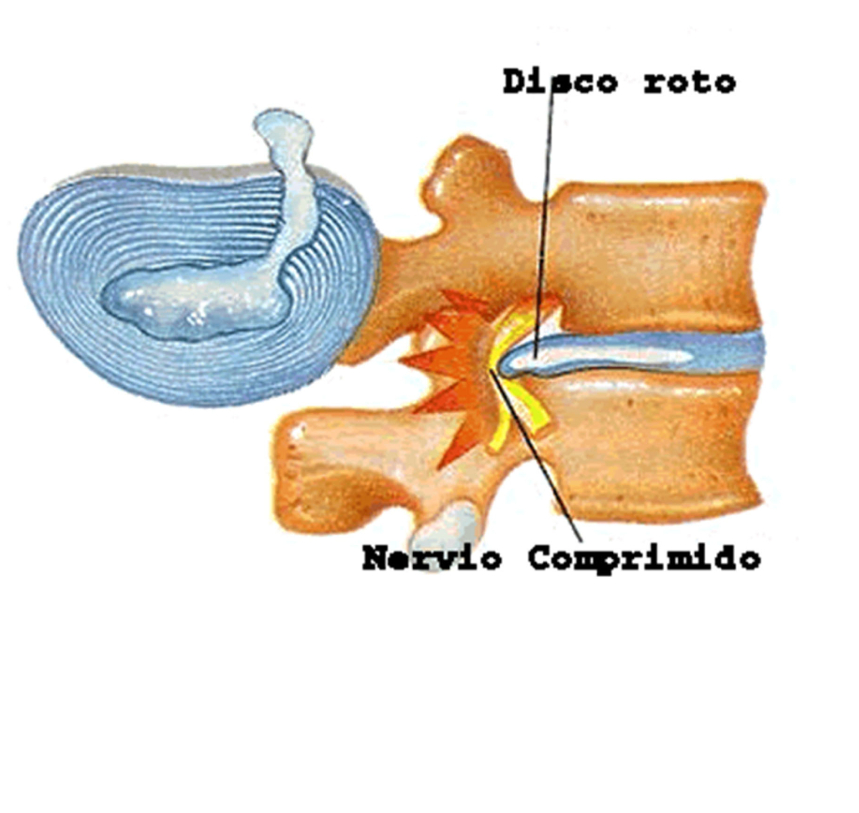

Las vértebras de la columna están separadas por discos que amortiguan y dejan espacio entre las vértebras. Los discos permiten el movimiento entre las vértebras y hacen de "amortiguadores". Tienen una zona central o núcleo pulposo y una periférica o anillo fibroso (Fig 2).

En la hernia discal lumbar lo que ocurre es que el núcleo se desplaza del centro a través del anillo fibroso y puede llegar a producir una protusión o una hernia discal (la diferencia es puramente el tamaño, la hernia es de mayor volumen que la protusión) (Fig 3).